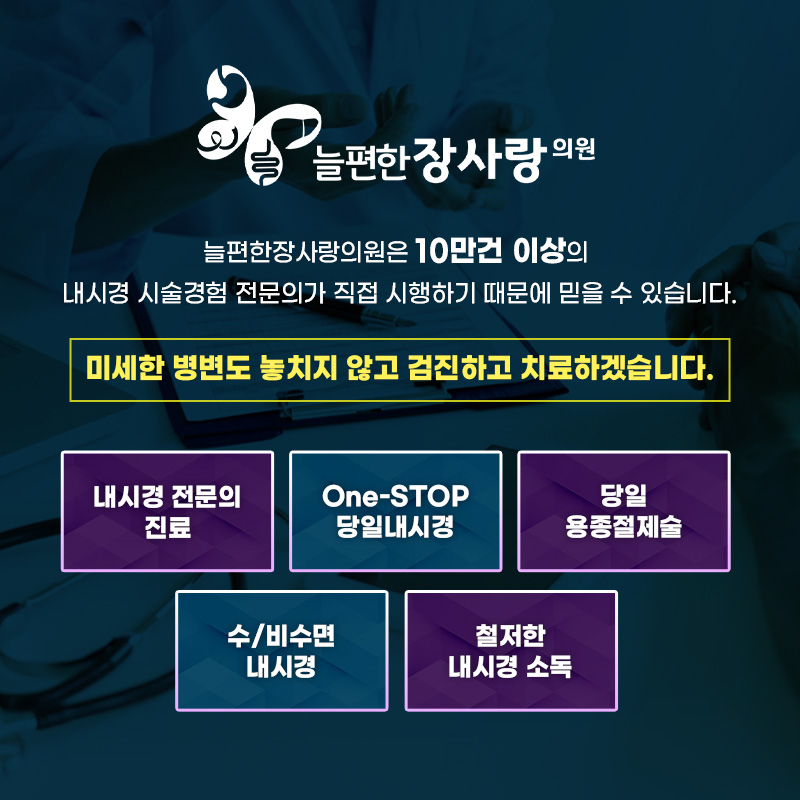

늘편한장사랑의원의

대장내시경 검사

늘편한장사랑의원에서는 풍부한 임상 경험을 바탕으로

여의사가 직접 대장내시경 검사를 진행합니다.

검사 과정 전반에 대해 불안과 부담을 줄일 수 있도록

검사 전후 충분한 설명이 함께 이루어집니다.

대장내시경 중 용종이 발견될 경우에는

상황에 따라 당일 용종 절제술이 가능해

검사와 치료를 한 번에 진행할 수 있습니다.

검사 시 고려할 수 있는 요소

내시경은 인체에 직접 삽입되는 검사인 만큼

위생 관리가 매우 중요합니다.

늘편한장사랑의원에서 사용하는 내시경 장비는

권고 지침에 따라 체계적인 세척·소독 과정을

거쳐 관리됩니다.